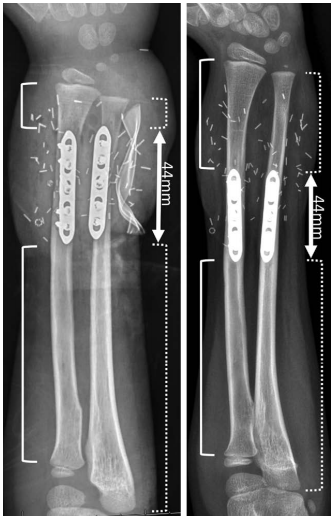

В 2020 году врачи, проводившие трансплантацию и продолжающие наблюдать Зиона Харви, опубликовали статью, в которой привели рентгеновский снимок его левой руки сразу после операции (слева – сразу после операции, справа – через 4 года). Достаточно даже беглого взгляда, чтобы отметить насколько увеличилась длина костей по сравнению с титановыми пластинами.

Главные сомнения врачей заключались в том, будут ли пересаженные руки расти вместе с пациентом. Спустя 5 лет после операции они были развеяны окончательно – пересаженные части рук пропорционально росли вместе с мальчиком.